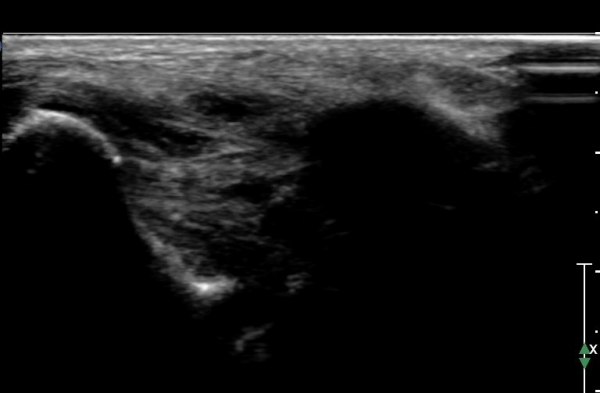

Àü°ÅºñÀδë ÇϺΠÁ¾´Ü¸é°Ë»ç¿¡¼­ Àü°ÅºñÀδëÀÇ Àú¿¡ÄÚ À§Ãø°ú Á·±Ùµ¿ÀÇ ¼ö¾×Àú·ù°¡

°üÂûµÈ´Ù(»çÁø 2, 3, 4).